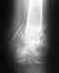

Здравствуйте, прошу посмотреть мои снимки. Что может быть не правильно? Каков исход данной операции? На данный момент прошло 3-мес. Вопрос по тыльному сгибанию стопы стоит остро потому как его практически нет,есть только 90'гр.

Нахожусь в стране с ограниченным количеством медучереждений и врачей, поэтому Ваше мнение будет очень ценным для меня

Поэтой одной проекции особых проблем не вино. Может, что-то не так на профильном снимке. Движения надо разрабатвать в любом случае.